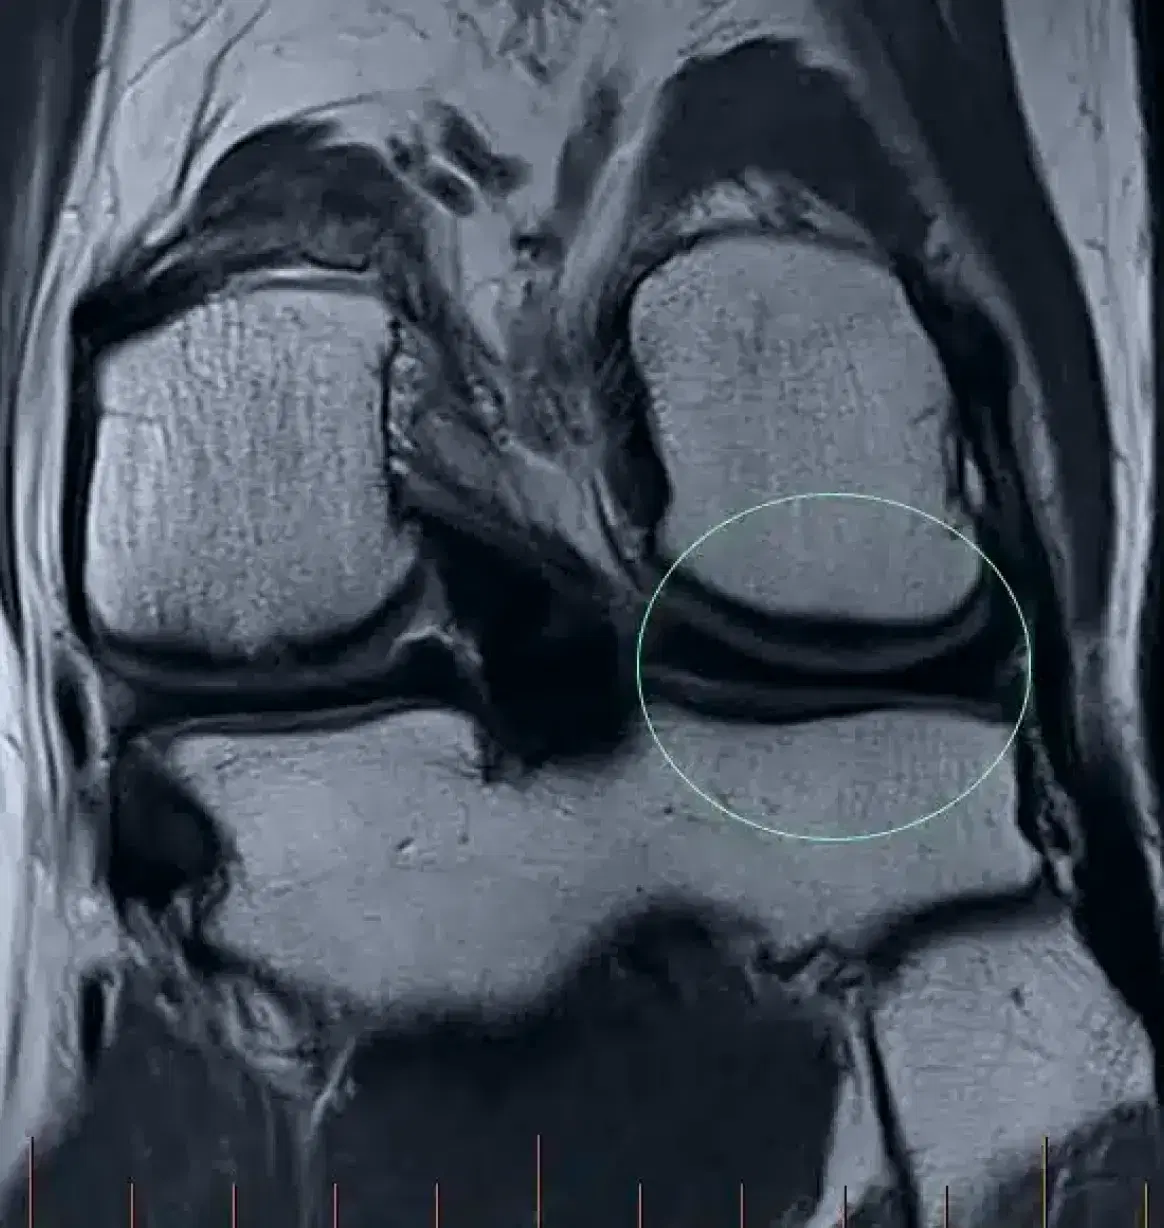

MRI scan of the left knee confirming the cartilage on the outer side of the knee is normal (circled)